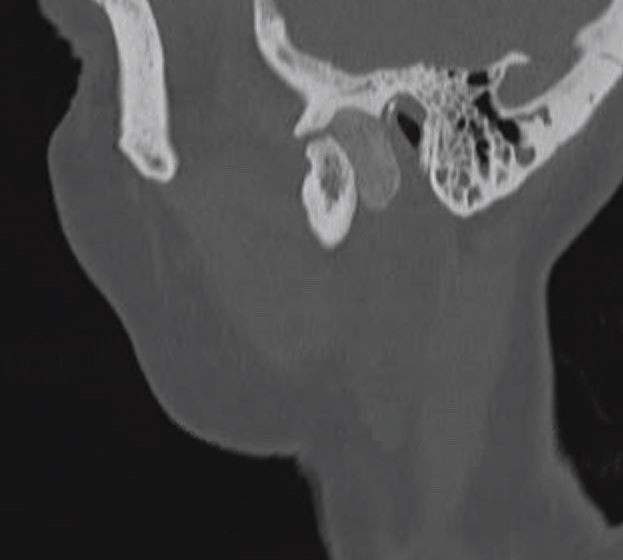

A 65-year-old patient presented with progressively worsening pain of the left face and jaw-locking for prolonged periods of the day. Examination revealed palpable swelling over the right TMJ and parotid region. Multiple cross-sectional imaging revealed a calcified mass lesion posterior to the right mandibular condyle suspicious of synovial osteochondromatosis (Fig. 1). A preauricular approach with temporal extension was planned and executed to access this tumour. The deeper layer of masseter was noted during dissection and a pictorial description is presented here (Fig. 2).